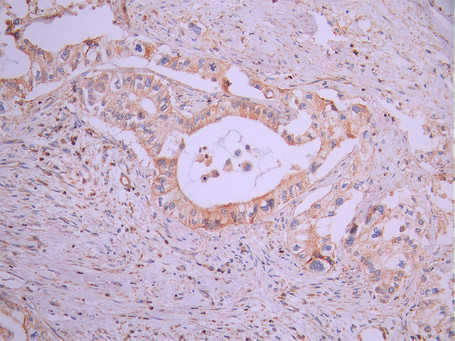

IHC image of CSB-RA272247A0HU diluted at 1:100 and staining in paraffin-embedded human pancreatic cancer performed on a Leica BondTM system. After dewaxing and hydration, antigen retrieval was mediated by high pressure in a citrate buffer (pH 6.0). Section was blocked with 10% normal goat serum 30min at RT. Then primary antibody (1% BSA) was incubated at 4°C overnight. The primary is detected by a Goat anti-rabbit polymer IgG labeled by HRP and visualized using 0.05% DAB.